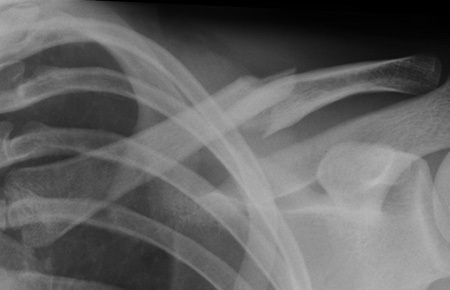

Transform Your Joints: Techniques to help to reduce arthritis discomfort

This topic focuses on Transform Your Joints: Techniques to help to reduce arthritis discomfort, Managing arthritis symptoms and improving joint health involves key strategies. Regular low-impact exercise like swimming or walking, along with stretching, can help to reduce pain and stiffness. Maintaining a healthy weight, practicing good posture, and wearing proper footwear also help. Eating an anti-inflammatory diet rich in omega-3s, fruits, and vegetables can further help to reduce inflammation, as can heat or cold therapy.